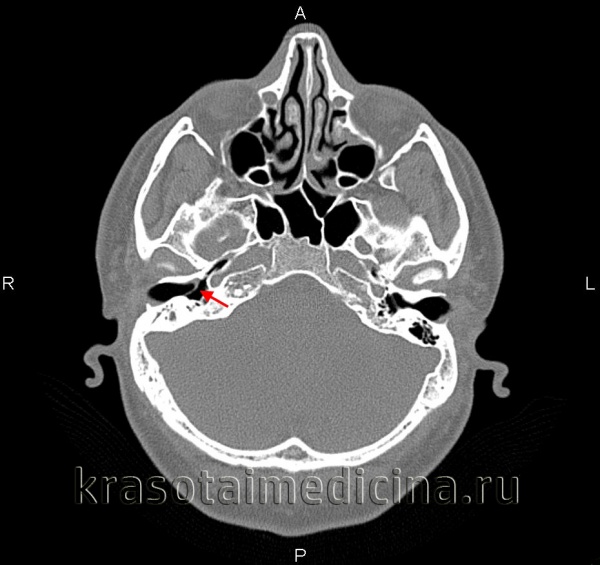

- Инструментальные исследования. Магнитно-резонансная томография или КТ височной кости позволяют обнаружить разрушение слуховых косточек, повреждение барабанной полости. С помощью рентгенографии черепа можно определить положение отдельных кальцинатов в составе тимпаносклеротических комплексов.